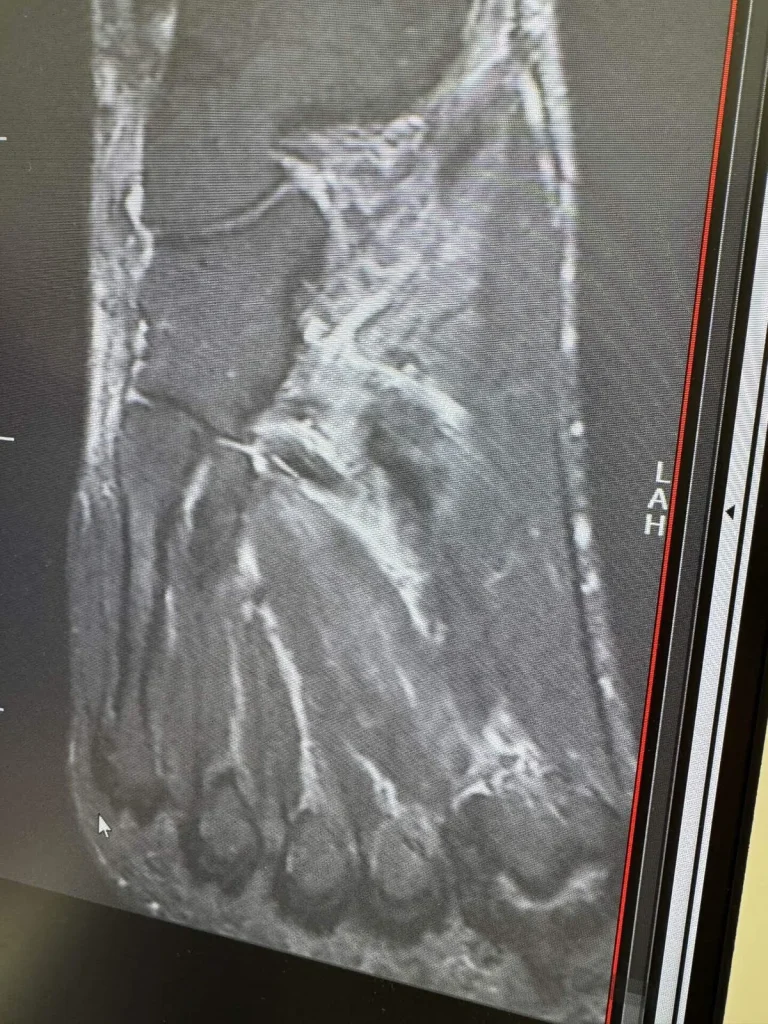

M R Iも撮って、診断結果は全治1ヶ月。

後日、検査してみると骨挫傷という骨折の一歩手前の状態でした。